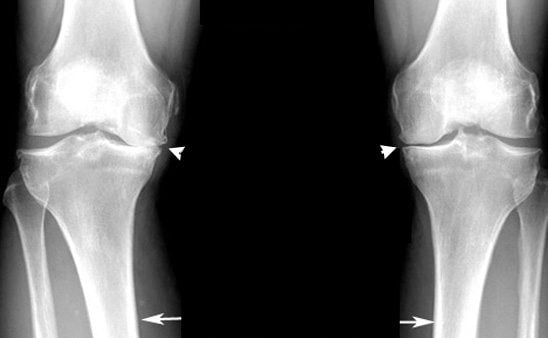

Разница в рентгенологических картинах:

- при артрозе плотность костной ткани повышается (остеосклероз), по краям суставных площадок образуются наросты-остеофиты, на фоне остеосклероза возможны единичные кистоподобные полости, окруженные склерозированным ободком;

- при артрите плотность кости уменьшается (остеопороз), формируются краевые дефекты костной ткани и множественные кисты.

Если данные лабораторных анализов указывают на артрит, а рентгенологическая картина характерна скорее для артроза, но имеет нетипичные черты, диагностируют артрозоартрит. В МКБ 10 такого заболевания нет, данный диагноз используется только в клинической практике.

- Для артроза коленного сустава характерна быстрая деформация. Разрушение хрящевой ткани при постоянных нагрузках на сустав приводит к появлению шипов, остеофитов, наростов. Колено постепенно перестает сгибаться, а отек и сильная боль мешают наступать на ногу.

Постепенно деформируются костные поверхности, которые разрастаются с образованием острых наростов — остеофитов. Костные шипы при смещении травмируют мягкие ткани, провоцируя развитие воспалительного процесса. В него вовлекаются синовиальная оболочка, суставная сумка, связки, сухожилия.